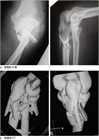

1. 定期レビューを行い、肘頭脱臼骨折をolecranon fracture dislocation (OFD)に変更した。その根拠についても記載した。

1. 直達外力による肘頭骨折と上腕三頭筋の牽引力によって起こる肘頭剝離骨折がある。

前者に対しては観血整復内固定術が行われることが多く、tension band wiring、intramedullary screw fixation、肘頭用アナトミカルロッキングプレートによるプレート骨接合術などの選択肢がある。

また後者に対する内固定法としては、骨片摘出+上腕三頭筋腱前進+その付着部の再縫着術が行われることが多い。